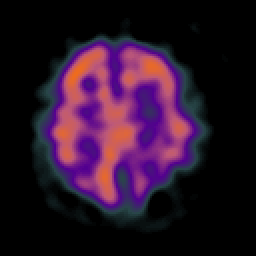

Alzheimer's disease: Perfusion SPECT -- Slice #35

[Home][Help][Clinical][Tour 1][Tour 2] Slice 35